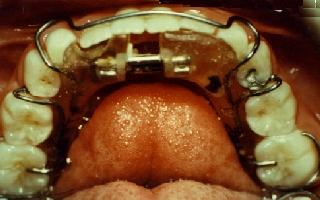

This patient had the beginnings of crooked teeth. We now know that by

utilizing modern orthodontic techniques at as early an age as possible,

many future problems can be alleviated and in some cases even totally

eliminated. For this little girl, we used a retainer called a Schwarz

appliance. The center screw in the appliance was slowly widened over

about a year's period. This changes the shape of the actual jawbone

during an active growth period. This expansion of the jawbone allows

for more room for the teeth and will either eliminate the need for

extracting permanent teeth or may even totally eliminate the need for

braces later on. |